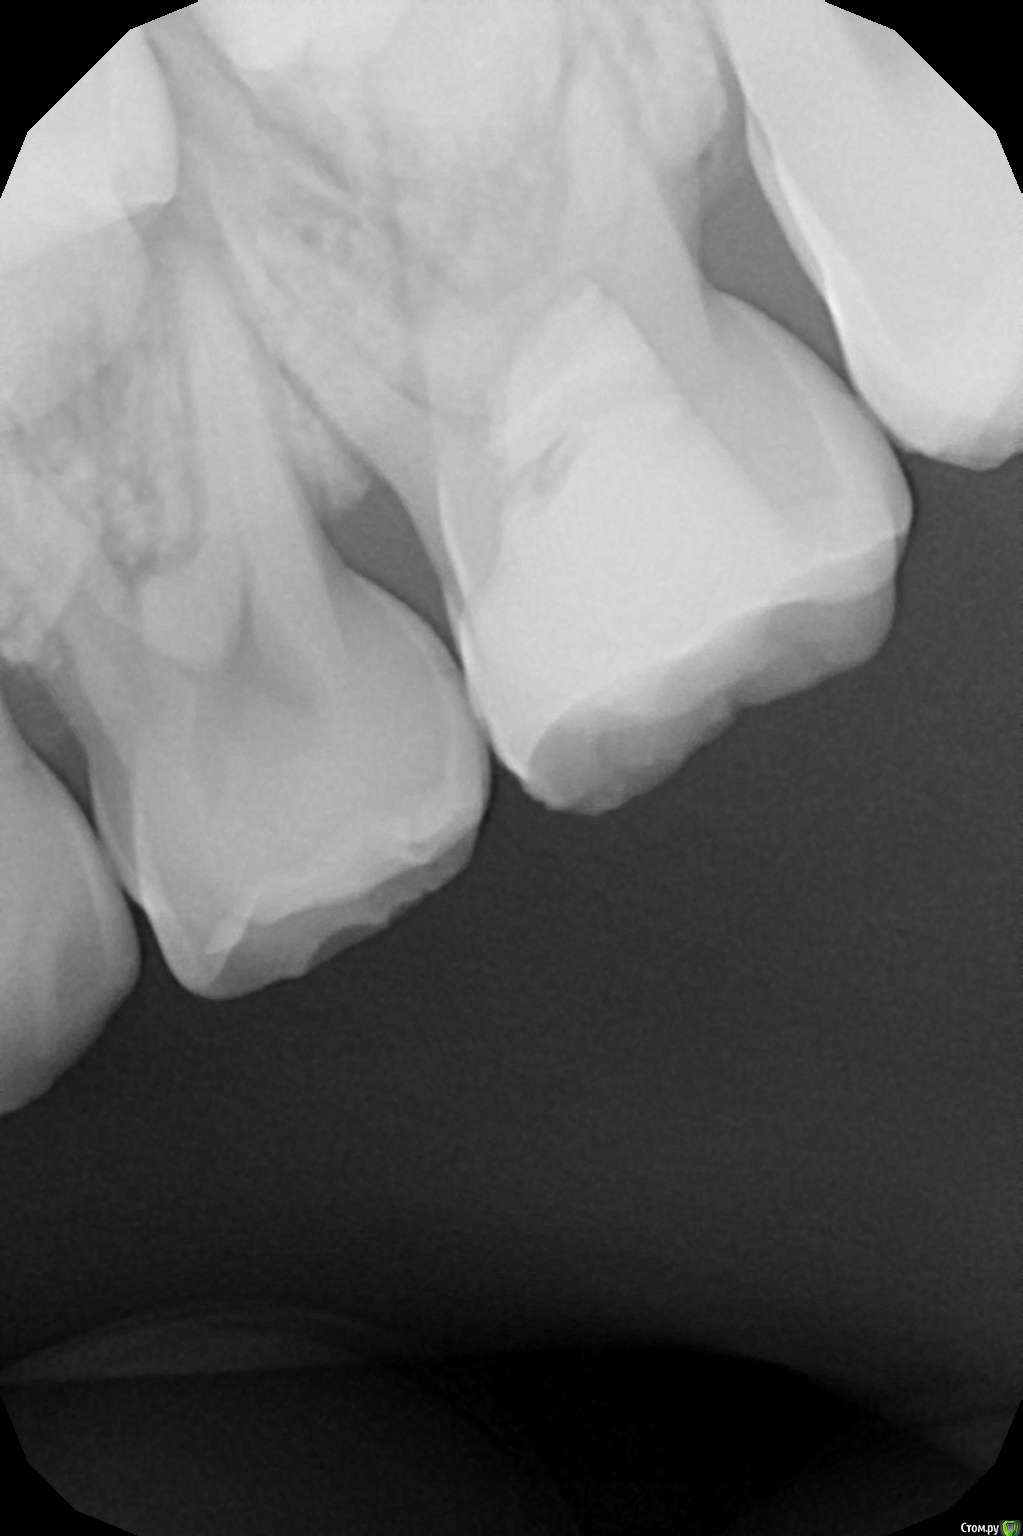

crown Опубликовано 19 октября, 2016 Автор Поделиться Опубликовано 19 октября, 2016 8 лет 2 месяца назад лечил 6.5 пульпитный с триоксидентом, сегодня отек в районе четверки и перкуссия ее болезненна, но она интактная. Решил полезть в 6.5, мб2 и мб1 прошел, закинул кальций, в небный не могу войти орет, дистальный вообще туго, облитерировалось по ходу все к чертям, пока оставил так. Но меня терзают сомнения, так как симптоматика вся на четвертом зубе и на снимке изменения в 6.4. Мамаша еще мозг выносит, сыпит вопросами как из пушки и тут не понятно то ли ребенка лечить то ли ей на вопросы отвечать. Ссылка на комментарий

Olga25 Опубликовано 14 ноября, 2016 Поделиться Опубликовано 14 ноября, 2016 Лично я бы удалила. там же очаг деструкции по бифуркации. прогноз для зуба неблагоприятный да еще и зачатком рискуете. жаль, что я еще не совсем разобралась да и с техникой не очень дружу. а так бы показала снимок на котором видно полную резорбцию корня зачатка постоянного 14 зуба после эндолечения 54 зуба. вернее на зачатке были видны следы пломбировочной массы, 54 зуб удалился, зачаток 14 прорезался, но корень рассосался. так и болтается шляпка коронки постоянного зубаЗдравствуйте!Я понимаю,что из-за проблем с мол.зубом может произойти и гибель зачатка,но при тяжел.осложнениях.В данном случае возможна гипоплазия. Почему корень постоянного зуба рассосался?Я таких случае не встречала.Какой прогноз для такого пост. зуба?? Ссылка на комментарий